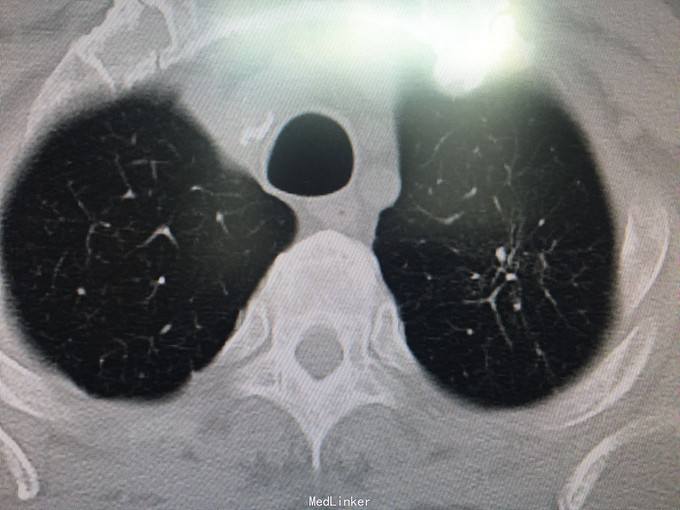

男性,70岁, 主诉:发现左肺上叶占位12个月 现病史:2014.10月患者出现胸背部疼痛不适,对症理疗未见好转。2014.11月出现咳嗽,咳痰带血丝,行胸部CT检查示:左肺上叶占位病变,恶性可能性大。2014.11.13患者行PET/CT检查提示:左肺上叶软组织密度肿块影伴周围片状密度增高影,代谢增高,考虑恶性病变伴周围炎性改变。纵隔内及左肺门多发淋巴结影,代谢增高,考虑为恶性病变转移。左肾上腺结节,代谢增高,考虑为恶性病变转移。第2胸椎棘突骨质破坏,代谢增高,考虑为恶性病变转移。肿瘤标志物:CA125 625 U/ml。因肿块位置较高,未行纤维支气管镜取病理,患者因年龄大,拒绝行肺肿物穿刺活检,故病理不明确。但根据肿瘤影像学形态及理化检测,怀疑为腺癌,建议患者行TKI靶向治疗,同时给予双磷酸盐治疗骨转移。患者口服TKI一个月后复查胸部CT肿块明显缩小,胸背部疼痛消失。患者现口服TKI约11个月,无明显咳嗽咳痰,无背部疼痛。近1周,患者诉偶尔咯鲜红色粘痰,伴有咽部及胸前区闷痛疼痛无明显咳嗽症状,为求复查而来诊。复查胸部CT较之前对比未见明显变化。复查肿瘤标志物:CEA、CA-125、NSE均未见异常。

查体:BP 165/75mmHg,双肺呼吸引清,未闻及干湿罗音,心音钝,心律齐,心率72次/分,各听诊区未闻及杂音。腹平,未见胃肠型及蠕动波,腹软,全腹无压痛,无反跳痛及肌紧张,肝脾肋下未触及,墨菲氏征(-),移动性肝肾区无叩痛,移动性浊音(-),肠鸣音4次/分。 辅助检查:肝胆脾彩超:未见明显异常。 胸部CT:较2015.8月对比未见异常,左肺上叶陈旧性改变。 肿瘤系列:CEA、CA-125、NSE均未见异常。